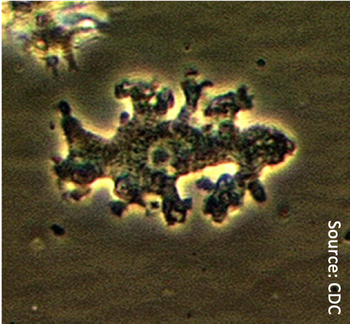

The recent death of a nasal irrigation user may have more to do with dirty water and/or improper use of the device, rather than a flaw with the approach.